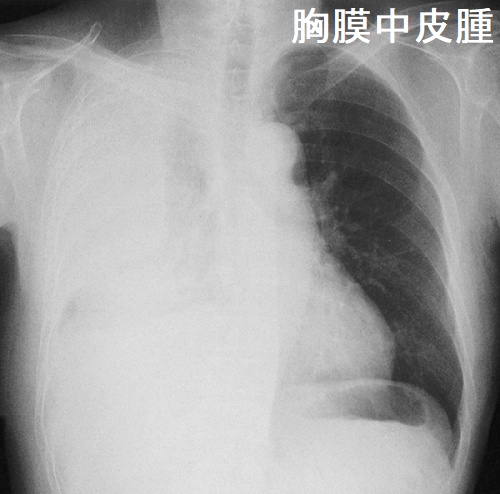

胸膜中皮腫

悪性中皮腫の甲状腺転移

悪性中皮腫のⅣ期には脳、脊柱、甲状腺に遠隔転移します。筆者の経験では、悪性中皮腫の甲状腺転移は、原発巣と同じような粗大な(巨大な)石灰化が見られます。[Pathol Res Pract. 1995 Jun;191(5):456-60; discussion 461-2.]